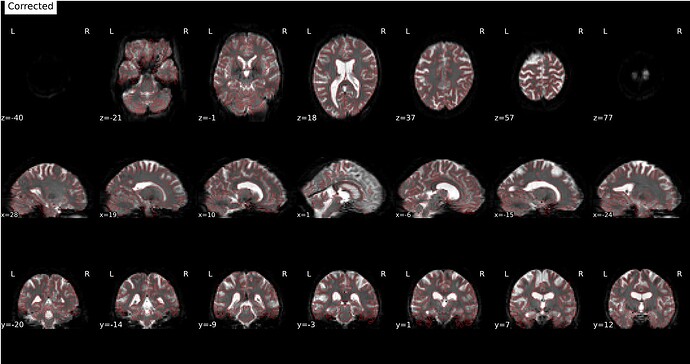

feed FMRIPREP with the undistorded, motion corrected

BOLD_u.nii.gz(4D timeserie corrected by SynBOLD-DISCO) and tell fmriprep to not run SDC (susceptibility distortion correction) on this data. That would work, but with the disadvantage of interpolating twice (= more smoothing) the data (once with SynBOLD-DISCO and once with fmriprep). Also motion correction will be done twice in that case: once with SynBOLD-DISCO and once with FMRIPREP, so you could not use the motion parameters calculated by fmriprep but instead need to use the motion parameters from Syn-BOLD-DISCO for your GLM and motion outliers. Or you could try to not run motion correction with SynB0-DISCO but I guess that would affect the accuracy of SDC with SynB0-DISCO. -